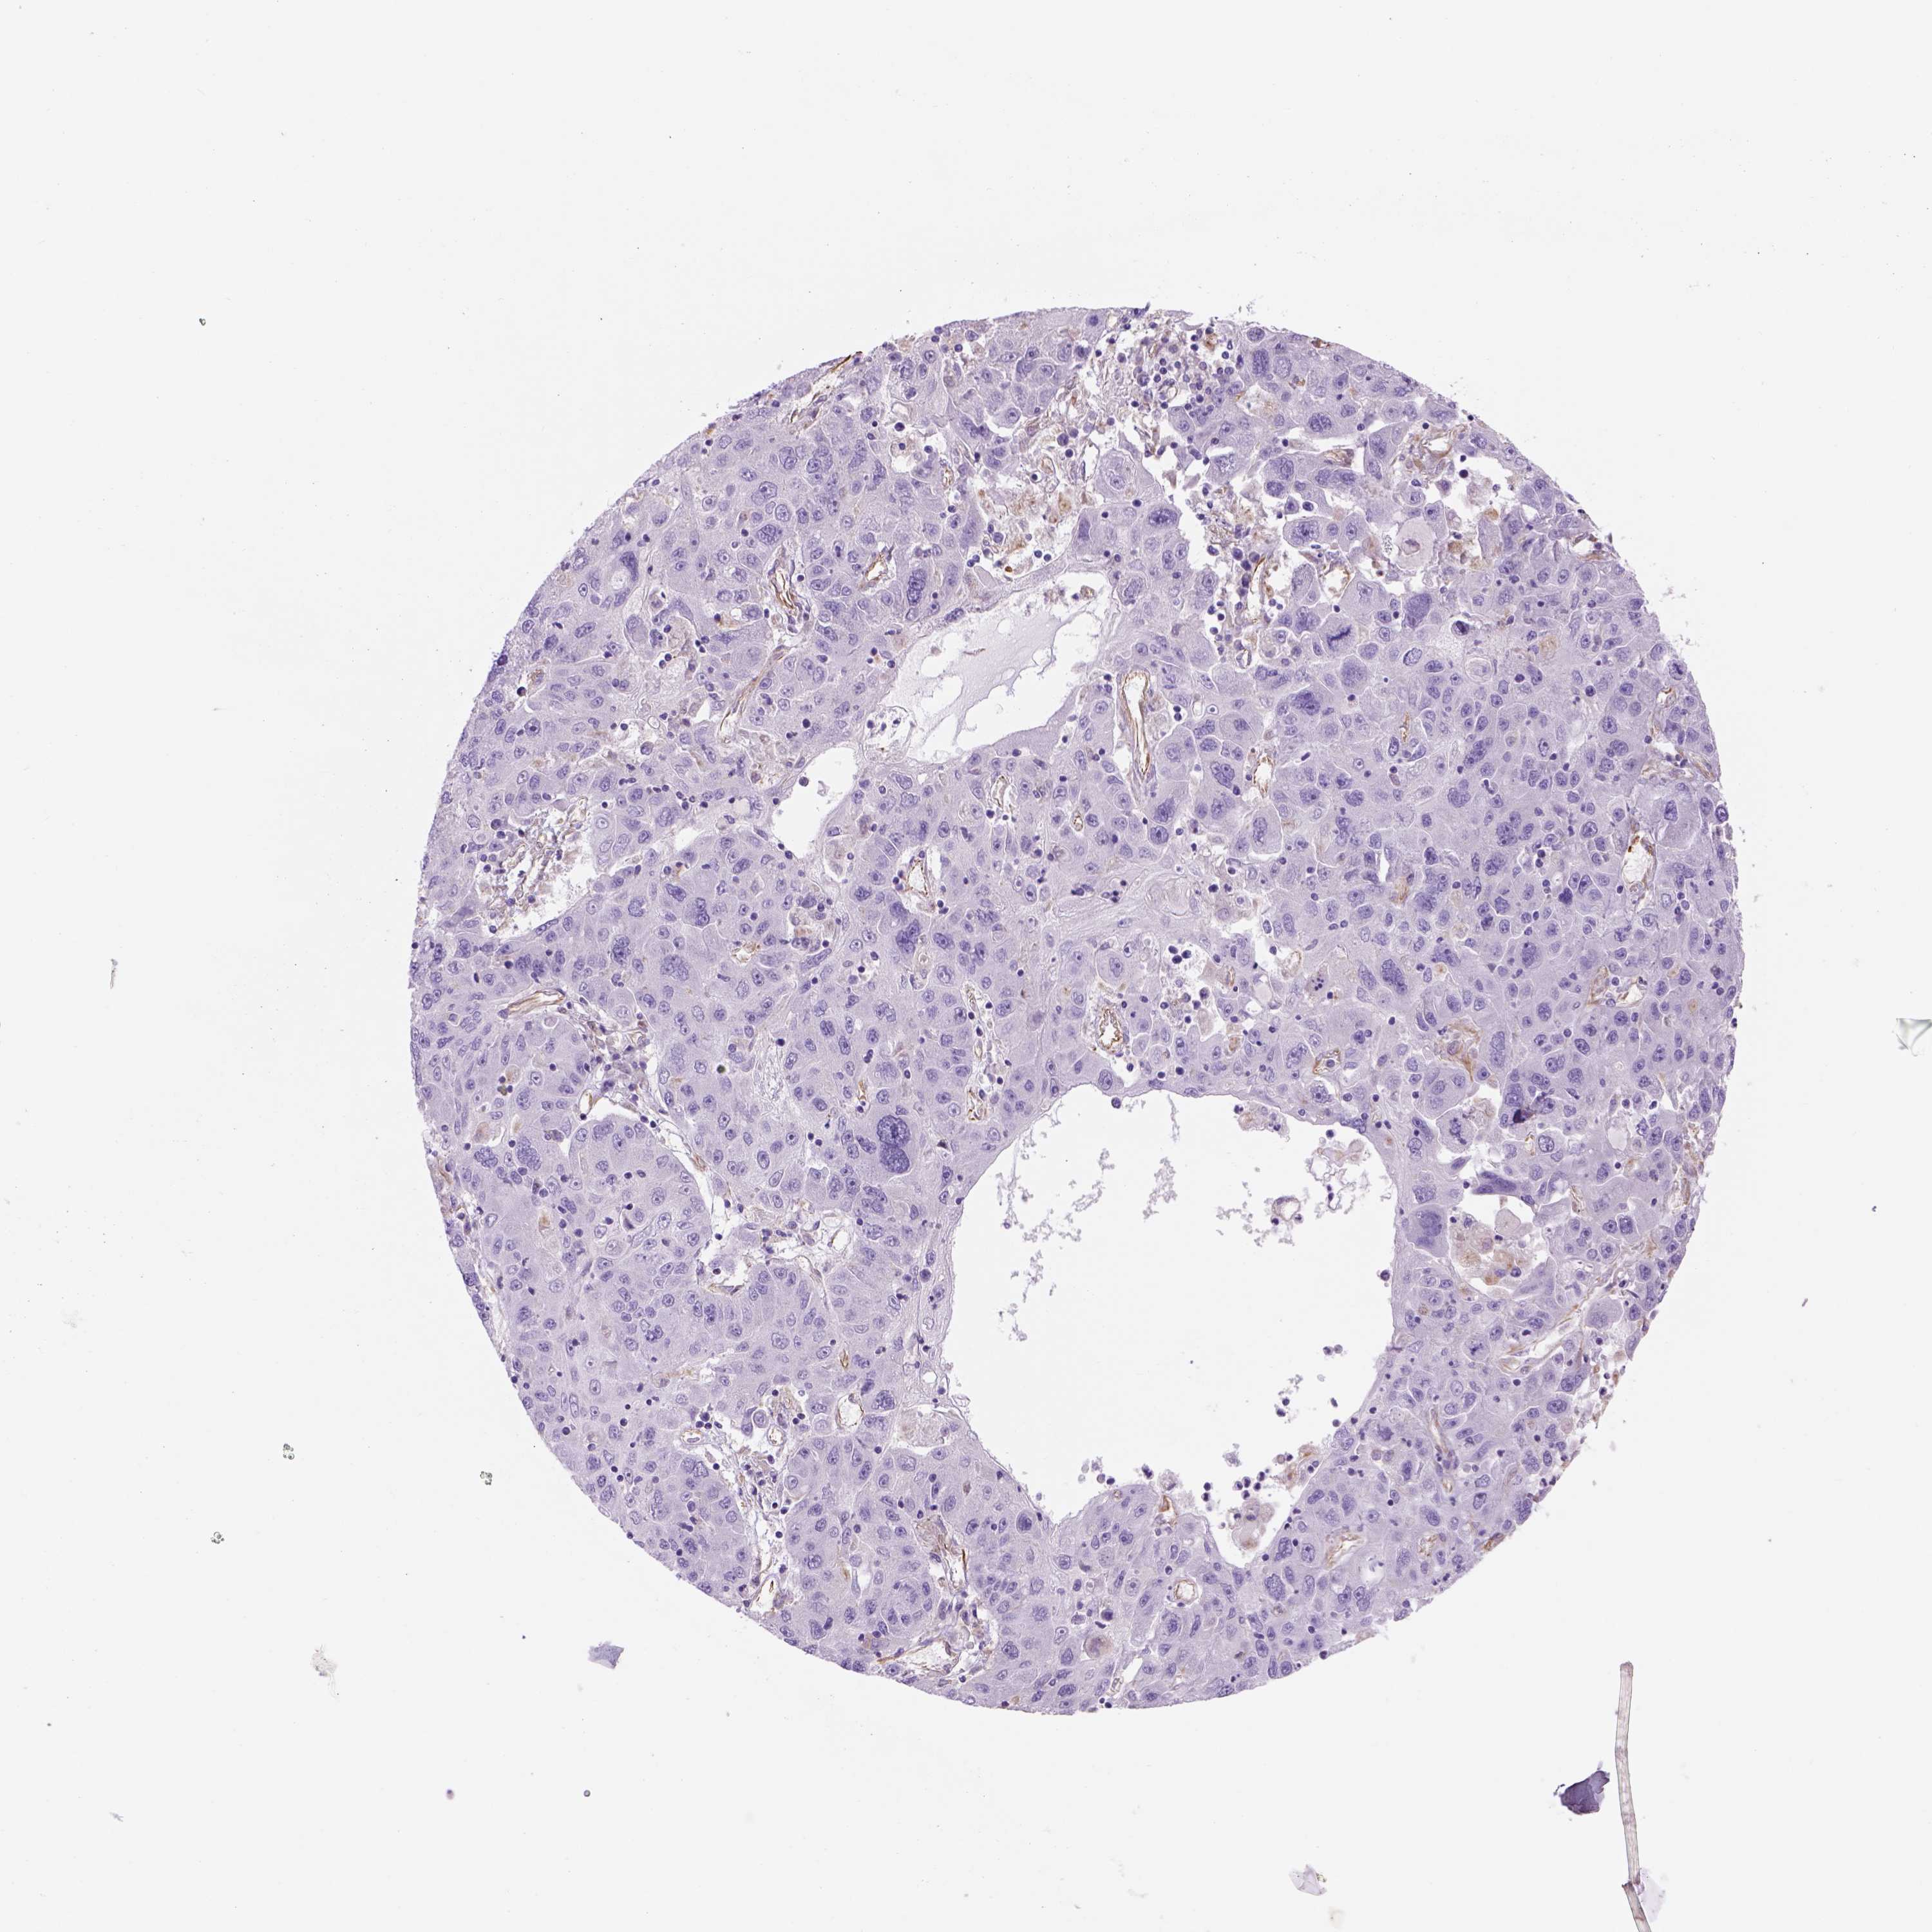

STOMACH CANCER - Protein expressioni

A mouse-over function shows sample information and annotation data. Click on an image to view it in a full screen mode. Samples can be filtered based on level of antibody staining by selecting one or several of the following categories: high, medium, low and not detected. The assay and annotation is described here.

Antibody stainingi

Antibody staining in the annotated cell types in the current human tissue is reported as not detected, low, medium, or high, based on conventional immunohistochemistry profiling in selected tissues. This score is based on the combination of the staining intensity and fraction of stained cells.

Each image is clickable and will lead to virtual microscopy that enables deeper exploration of all samples and also displays staining intensity scores, fraction scores and subcellular localization as well as patient and tissue information for each sample.

Antibody HPA066197

Staining

High

Medium

Low

Not detected

Intensity

Strong

Moderate

Weak

Negative

Quantity

>75%

75%-25%

<25%

None

Location

Nuclear

Cytoplasmic/membranous

Cytoplasmic/membranous,nuclear

Adenocarcinoma, NOS